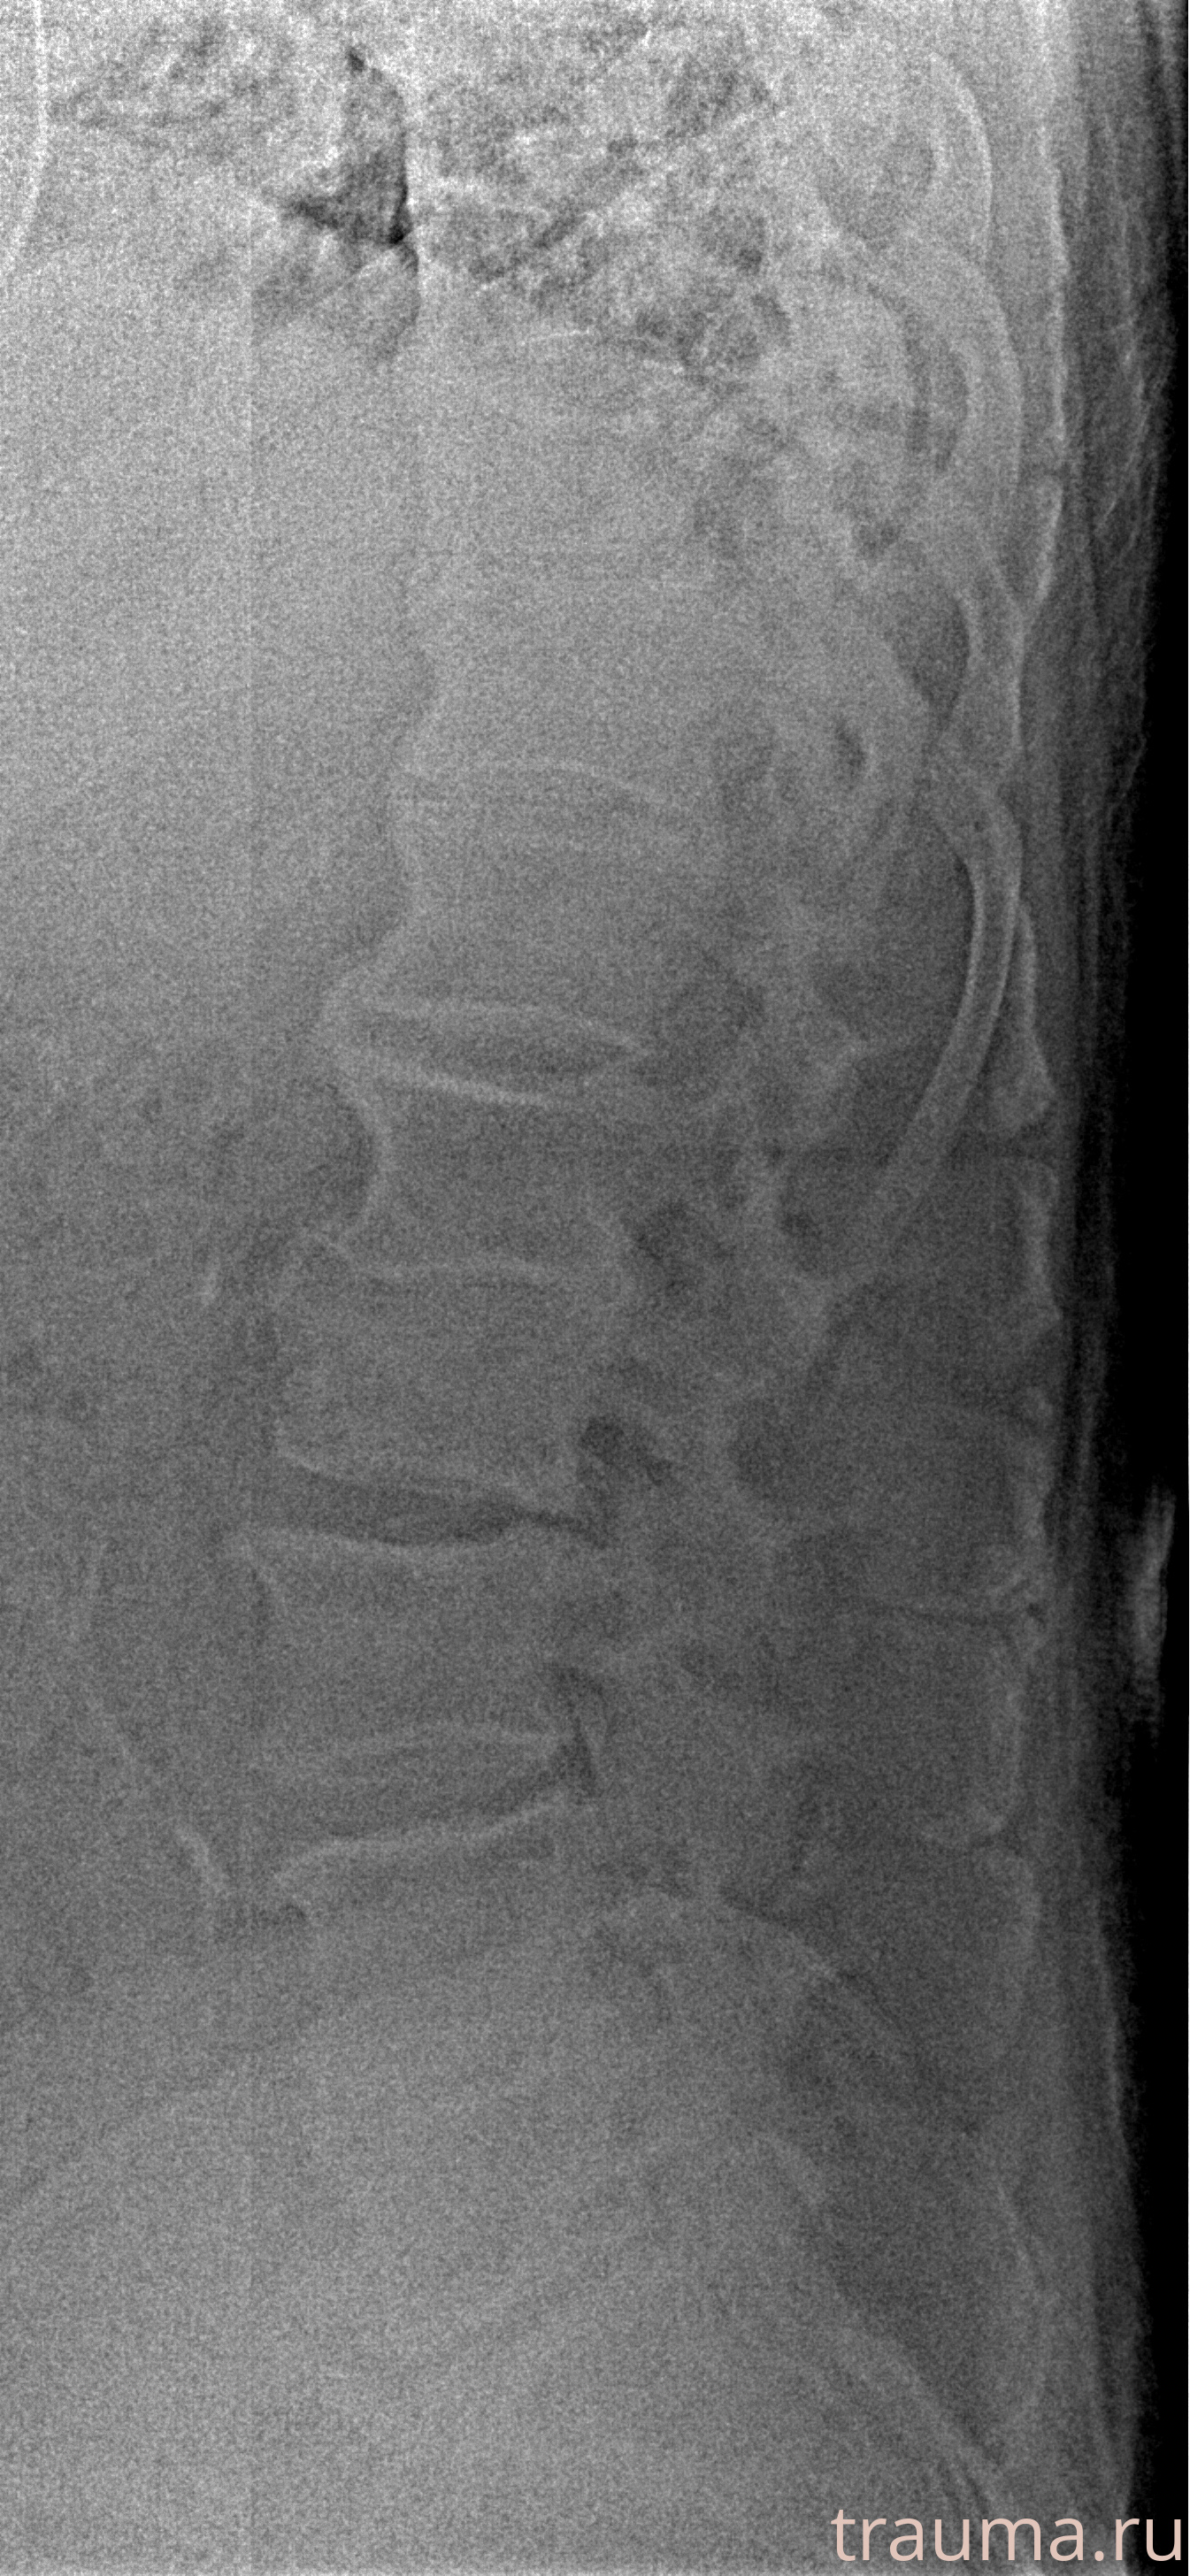

Рентген на дому: по вашему адресу приезжает врач-рентгенолог, травматолог-ортопед с мобильным рентгеновским аппаратом, проводит диагностику травмы или заболевания, делает необходимые рентгенограммы, дает рекомендации по дальнейшему лечению. Получить качественные снимки в домашних условиях возможно благодаря уникальной методике, разработанной МосРентген Центром для института  Склифосовского